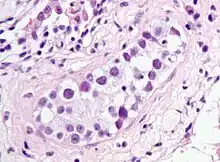

Intratubular germ cell neoplasia. H&E stain. | |

GCNIS is not palpable, and not visible on macroscopic examination of testicular tissue. Microscopic examination of affected testicular tissue most commonly shows germ cells with enlarged hyperchromatic nuclei with prominent nucleoli and clear cytoplasm. These cells are typically arranged along the basement membrane of the tubule, and mitotic figures are frequently seen. The sertoli cells are pushed toward the lumen by the neoplastic germ cells, and spermatogenesis is almost always absent in the affected tubules. Pagetoid spread of GCNIS into the rete testis is common. Immunostaining with placental alkaline phosphatase (PLAP) highlights GCNIS cell membranes in 95 percent of cases. OCT3/4 is a sensitive and specific nuclear stain of GCNIS.[3]